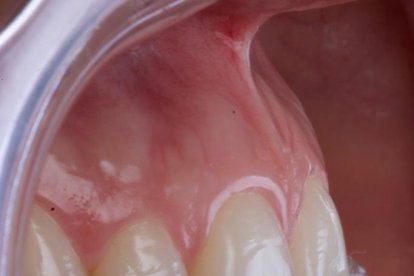

Si el profesional tiene identificado que alguna persona está bruxando, lo que en ocasiones hace es colocarle un protector (guarda oclusar, placa neuromiorelajante). Esto no significa que el paciente deje de bruxar, sino que “en lugar de desgastar sus dientes, desgasta el aparato, y así los protege”.